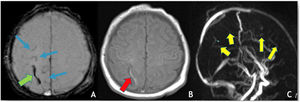

The most common trigger for cerebral venous thrombosis was infection (50%). There were two cases of acute mastoiditis, two cases of bacterial meningitis (Fig. 2), one case of deep neck abscess and one case of meningoradiculitis due to herpes-7. Nephrotic syndrome is a well-known prothrombic trigger and was found in two cases. The use of oral contraceptive was considered as a possible trigger in the adolescent females. One of them also has Down syndrome with obesity and hypothyroidism which may have also been contributing factors.

(A) Coronal T2 demonstrates absent flow void in the right transverse sinus (yellow arrow); (B) MRV (3D reconstruction), exhibits absent flow signal in the right transverse and sigmoid sinuses as well as ipsilateral jugular vein (red arrows); (C) Axial T1post-GAD showing diffuse pachymeningeal and leptomeningeal enhancement (blue arrows).